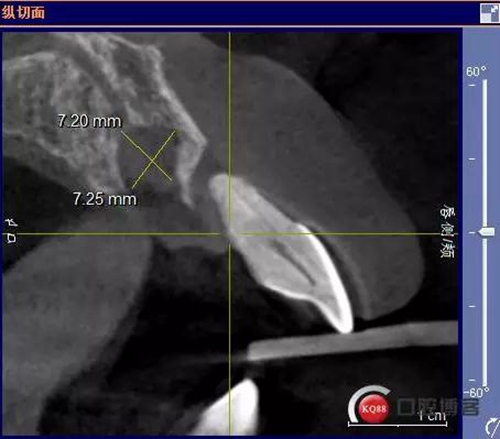

患者:王XX 年齡:42 上前牙松動數(shù)年,從未做過任何處理,今來院就診;檢查:CBCT示上前牙區(qū)顎側(cè)一大小約7x7mm囊腫;治療計劃:即刻種植同期摘除囊腫

術(shù)前CBCT